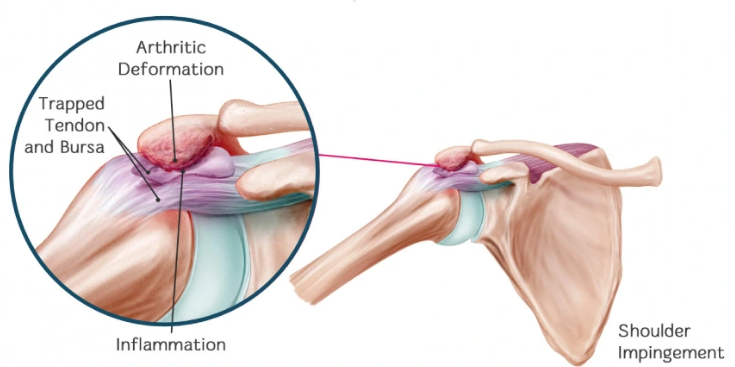

어깨 충돌 증후군은 어깨 관절에서 견봉(어깨뼈의 돌출 부위)과 회전근개(어깨 힘줄)의 사이 공간이 좁아지면서 이 힘줄들이 움직일 때마다 견봉과 충돌하여 염증과 통증을 유발하는 질환입니다. 주로 노화, 퇴행성 변화, 외상, 그리고 어깨를 많이 사용하는 반복적인 동작으로 발생할 수 있습니다. 초기에는 참을 수 있는 정도의 통증으로 시작하지만 방치하면 회전근개 파열까지 이어질 수 있어 초기에 정확한 진단과 치료가 중요합니다.

♦어깨 관절 부위인 견봉과 회전근개의 공간이 좁아지면서 힘줄이 반복적으로 충돌하는 경우

X-ray: 견봉뼈의 돌출이나 뼈 모양 이상, 관절 간격 등을 확인하여 충돌 증후군 외 다른 뼈 관련 이상 질환 감별.